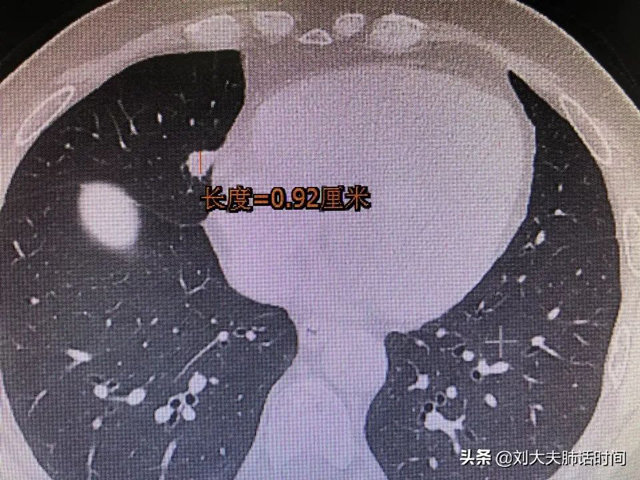

按照病灶大小:

直径<5mm的肺结节称为微小结节

直径5-10mm之间的肺结节为小结节

肺结节中,95%都是良性结节,不需要做手术,只有5%是恶性结节(肺癌)。判断肺结节是良性还是恶性,观察3个月,比较肺结节的外部结构和内部特征非常重要。